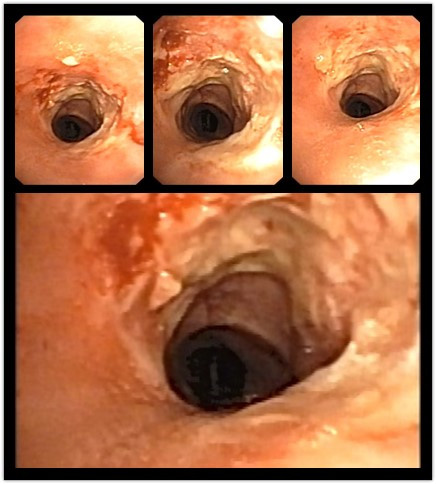

她当时以为是恶性肿瘤转移,在多家医院治疗效果都不理想,辗转到了广西壮族自治区南溪山医院求医,呼吸与危重症医学科副主任屈东明为她进行电子支气管镜检查时发现,因为她是瘢痕体质,上次舌癌手术气管切开后出现了气管狭窄,距声门下约 4 cm 处狭窄只有 5 mm,连正常人的三分之一都不到。

于是屈东明副主任带领团队与麻醉科共同为她采取了局麻下的经电子支气管镜微创手术治疗,在电子支气管镜下把气管内疤痕组织切开,切除增生的疤痕组织并冷冻处理,使气管恢复到 15 mm 左右,术后高奶奶感觉呼吸困难的症状就消失了,术后当天就能自行下床活动了,术后一周就康复出院了。

术前照片

术后照片

据屈东明副主任介绍,气管狭窄是不可逆转、进行性加重的病变,常见的症状是气道梗阻导致的呼吸困难,呼吸道内分泌物增多有可能导致气管完全梗阻,甚至窒息死亡。